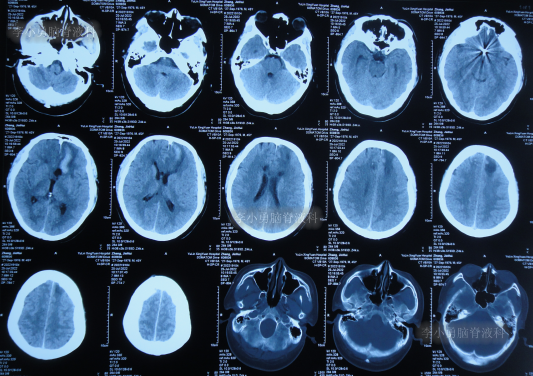

脑动脉瘤栓塞术后4天即2022年7月12日,查头颅CT示仍有积血(图-4)。

图-4:2022年7月12日头颅CT

拔除引流管后10天即2022年7月25日(脑动脉瘤栓塞术后17天),查头颅CT示脑室周水肿,仍有少量积血(图-5);仍间断发热,且脑脊液白细胞仍高,脑脊液浑浊。

图-5:2022年7月25日头颅CT